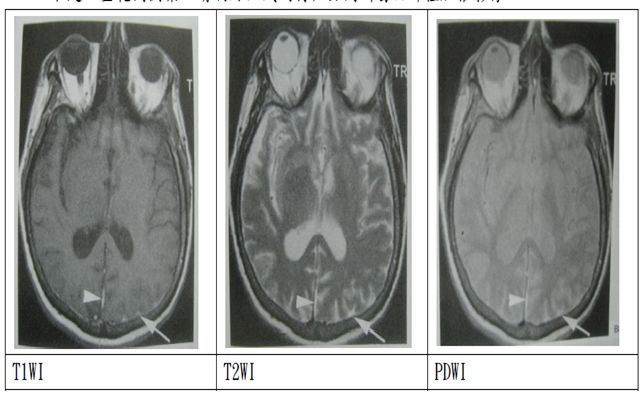

T1WI:

取短TR,使脂肪等短T1組織可充分弛緩,而腦脊髓液等長T1組織所呈現的弛緩量相對較少。

T2WI:取長TE,會將訊號中T1效應排除。長TE可凸顯出液體等橫向弛緩較慢的訊號。

PDWI:

稱作質子密度加權影像(proton density weighted image),主要是由組 織的質子密度差來產生影像對比度。使用長TR可使組織的縱向磁量充分 弛緩,以削減T1對訊號的影響,使用短TE是可以削減T2對影像的影響